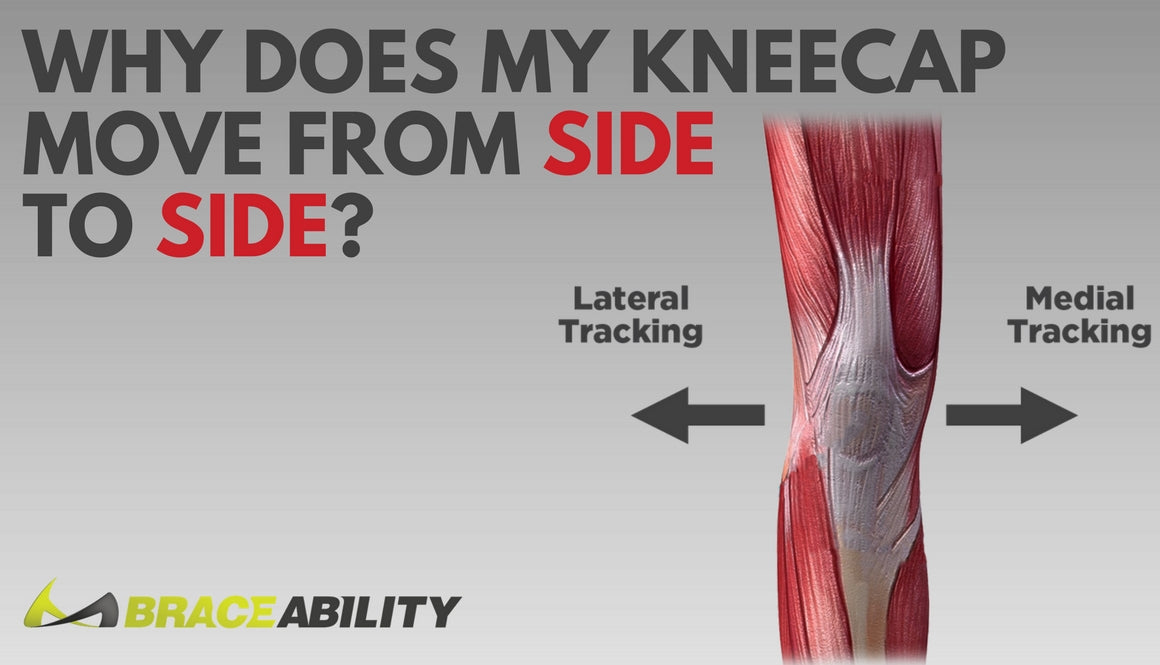

Luxating patella Wikipedia best sale, Floating Knee Physiopedia best sale, Kneecap Instability Medial vs Lateral Patellar Dislocation best sale, Floating Knee Cap recurrent patellar dislocation knee cap Flickr best sale, Floating Knee What Is Floating Knee best sale, Luxating patella in dogs PDSA best sale, Patella Slipping Knee shellylildoggrooming best sale, The Story of the Floating Knees Sanna Dyker best sale, Surgery and non surgical treatments for chronic knee cap best sale, Floating knee A modified Fraser s classification and the results best sale, PDF Bifocal disruption of the knee extensor apparatus best sale, Fraser s classification of floating knee. Download Scientific best sale, Patellar Luxation a Painful Preventable Problem for Small Dogs best sale, Kneecap Instability Medial vs Lateral Patellar Dislocation best sale, Floating Knee Practice Essentials Pathophysiology Etiology best sale, Floating Knee PDF best sale, Patellar Instability Knee Sports Orthobullets best sale, Luxating Patella in Dogs Knee Dislocation Symptoms Causes best sale, Floating Knee Practice Essentials Pathophysiology Etiology best sale, Knee Pain Can Physiotherapy Help The Physio Lounge Blog best sale, Patellar Dislocations Everything You Need To Know Dr. Nabil Ebraheim best sale, Chondromalacia Harvard Health best sale, Kneecap Instability Medial vs Lateral Patellar Dislocation best sale, Frontiers The current issues and challenges in the management of best sale, Patella Kneecap Anatomy and Function best sale, Luxating Patella in Dogs best sale, Floating Knee PDF best sale, Patellar Fractures Broken Kneecap OrthoInfo AAOS best sale, Management of the Floating Knee in Polytrauma Patients best sale, Luxating Patella in Dogs A Complete Guide Dr. Buzby s ToeGrips best sale, Floating Knee Practice Essentials Pathophysiology Etiology best sale, Luxating Patella in Dogs Signs Surgery Cost More Pawlicy Advisor best sale, ii The floating knee in adults and children ScienceDirect best sale, Patellofemoral Instability Kneecap Knee Joint Problems best sale, Patellar Instability symptoms causes best treatment best sale.